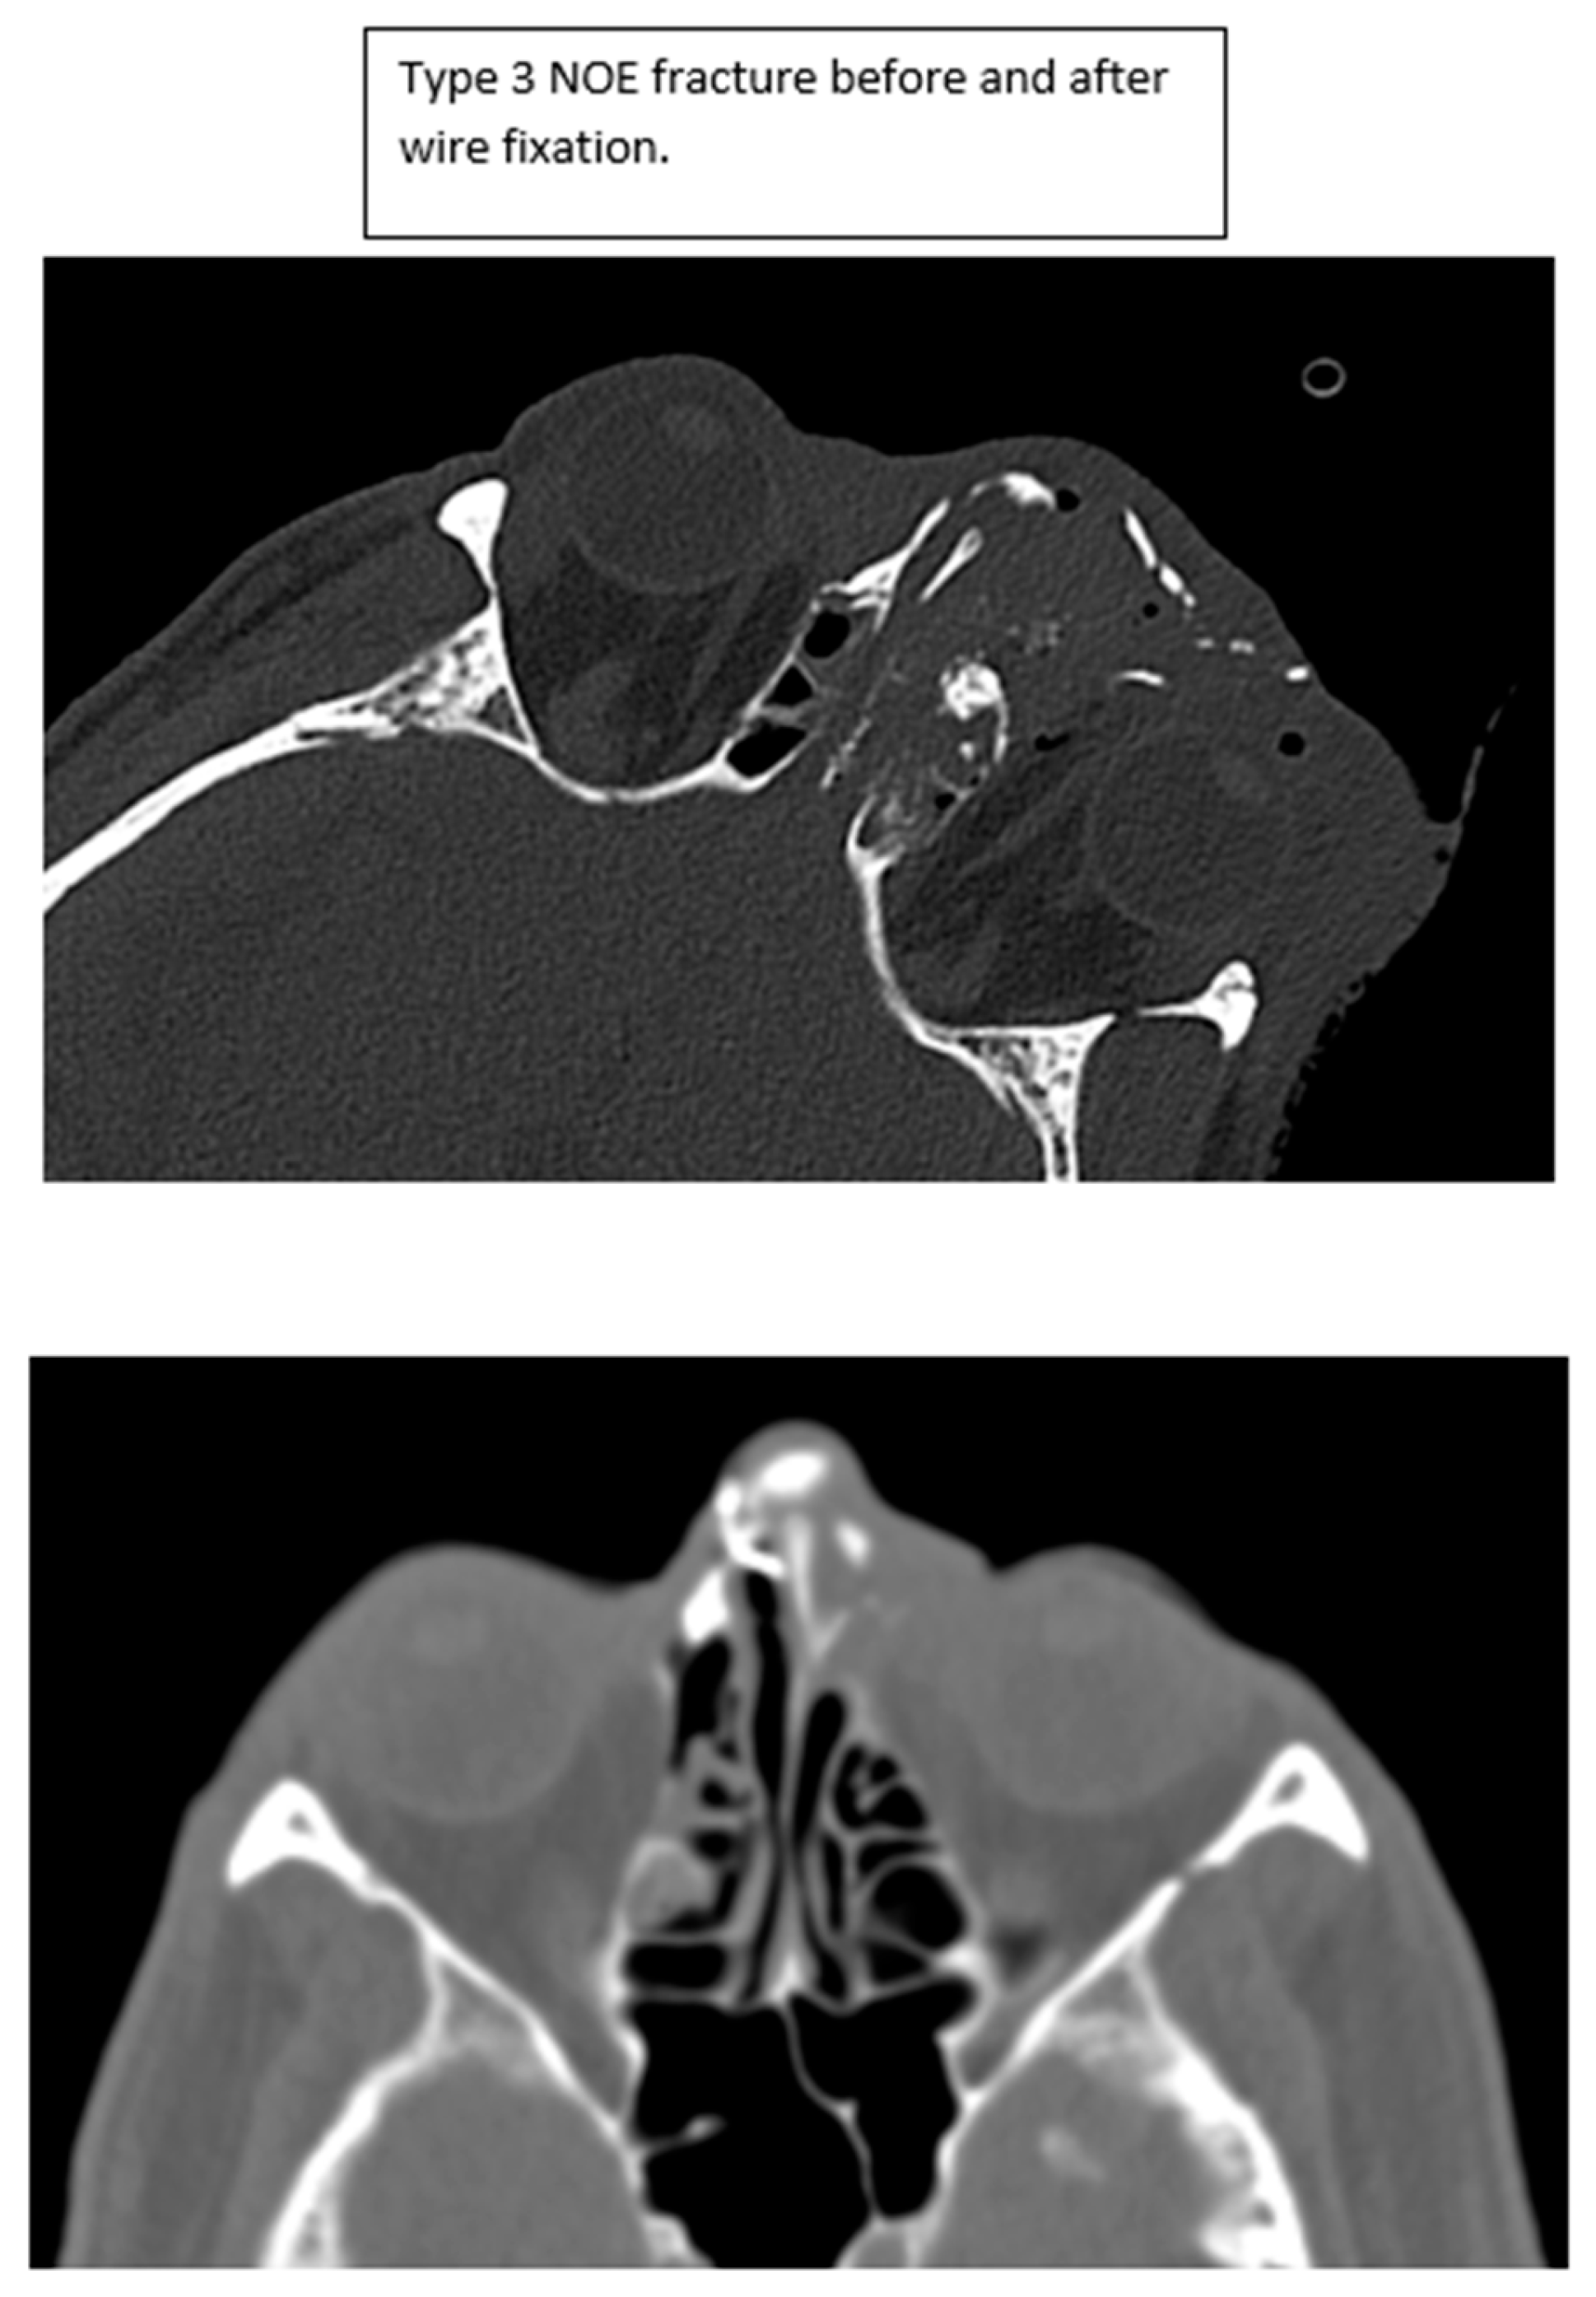

Figure 5. Type 3 NOE fracture CT imaging before and after intercanthal wiring.